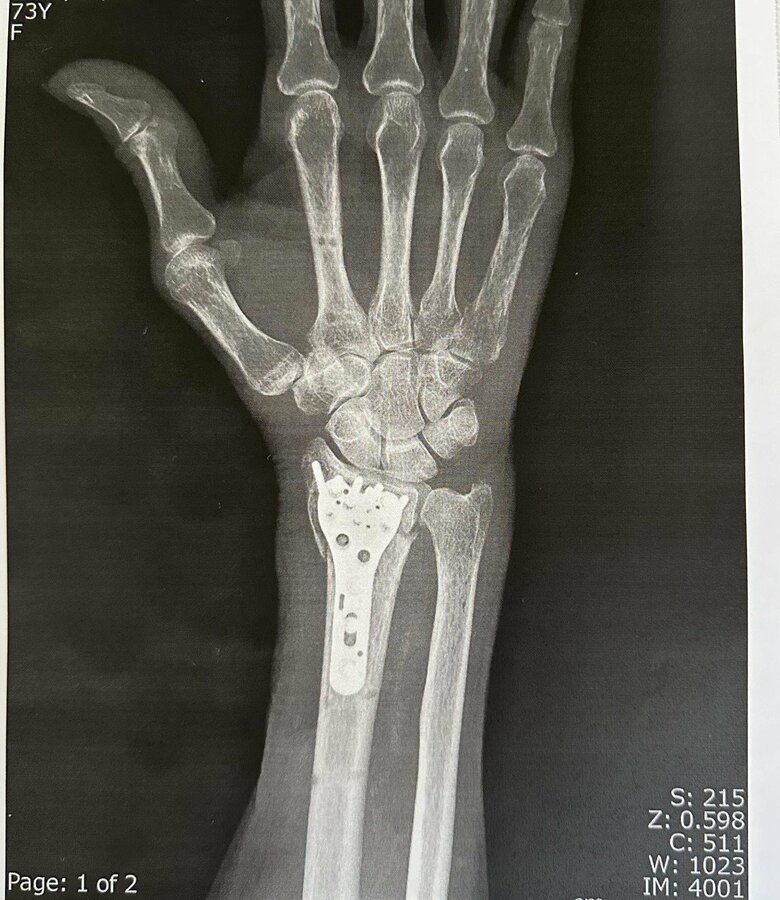

今年の春、転倒し大ケガ。腕をプレートで固定している様子が見て取れる

19/22

転倒し腕を大ケガ

22/22

転倒し腕を大ケガ。骨がズレているのがわかる